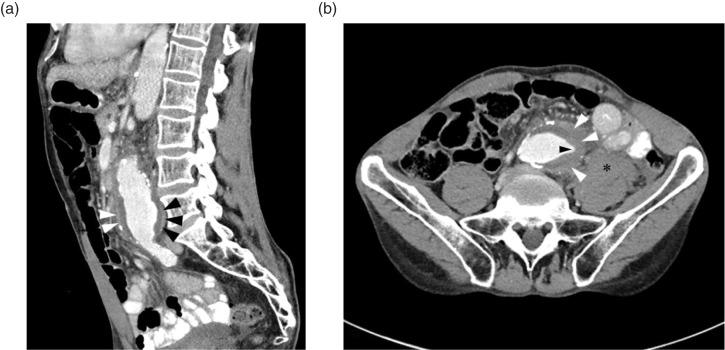

Abdominal aortic aneurysm (AAA) may present with subtle clinical findings. Recognition of the imaging features of an impending rupture is key for timely diagnosis. This report reviews the classic computed tomography findings of impending AAA rupture and presents a recent case which illustrates the key features.

腹主动脉瘤(AAA)可能表现出细微的临床症状。识别即将破裂的影像学特征是及时诊断的关键。本报告回顾了腹主动脉瘤即将破裂的经典计算机断层扫描结果,并呈现了一个近期病例以说明关键特征。